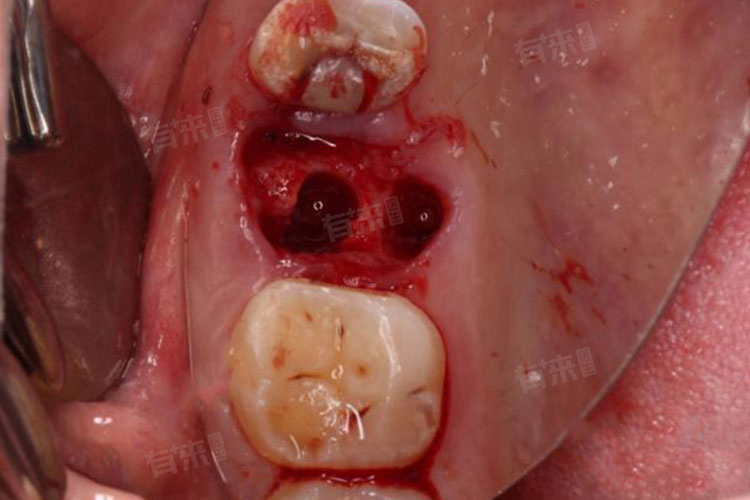

3、缝合止血:若拔牙创口较大、出血较多,或存在牙龈撕裂等情况,常规压迫和药物止血无效时,需进行缝合止血。医生会在局部麻醉下,使用缝合线对创口进行缝合,通过拉拢创口边缘,使血管断端紧密贴合,减少出血空间,促进血凝块形成。缝合后仍需配合压迫止血,并遵医嘱在一定时间后拆线。

4、局部填塞止血:对于拔牙窝内出血难以控制的情况,可采用局部填塞止血。使用明胶海绵、碘仿纱条等填塞材料,填入拔牙创口内,起到机械压迫和促进凝血的作用。这些材料能够为血凝块形成提供支架,同时隔绝外界刺激,防止血凝块脱落。填塞后需告知患者避免触碰创口,防止填塞物移位,待创口初步愈合后,再逐步取出填塞材料。